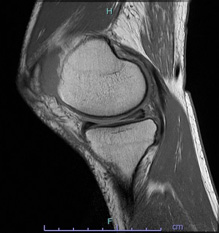

• 画像:損傷後内側半月板MRI画像(側面)

損傷後内側半月板MRI画像(側面)

• 画像:損傷後内側半月板MRI画像(正面)

損傷後内側半月板MRI画像(正面)